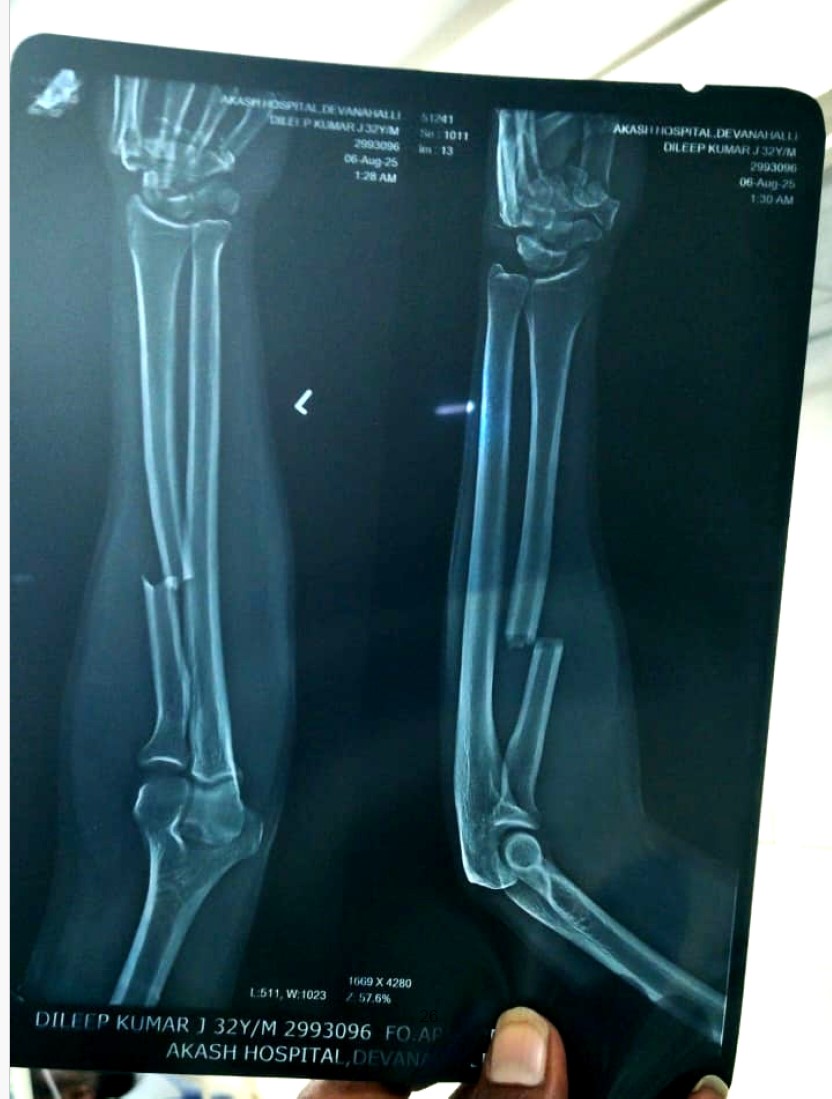

Dileep J, a 31-year-old young man, met with a devastating road traffic accident (RTA) that left him with severe trauma to his left brachial plexus. This injury has led to complete motor loss (0/5) and sensory loss across multiple nerve levels (C5 to T1), affecting his ability to use his arm and shoulder. MRI and CT reports reveal extensive damage, including thickened nerve trunks, fluid accumulation, and edema in both superficial and deep tissues of the neck and chest.

Despite the severity, his spinal cord remains intact, giving hope for recovery if prompt medical intervention is provided. Doctors have recommended further treatment and a follow-up scan after three months to assess nerve healing and potential for surgical repair or advanced therapy.